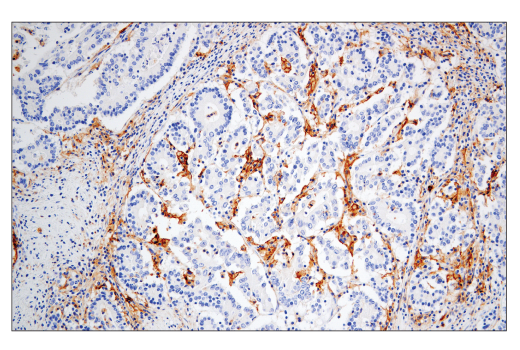

W, IHC-Bond, IHC-P, IF-IC

W: Western Blotting IHC-Bond: IHC Leica Bond IHC-P: Immunohistochemistry (Paraffin) IF-IC: Immunofluorescence (Immunocytochemistry)